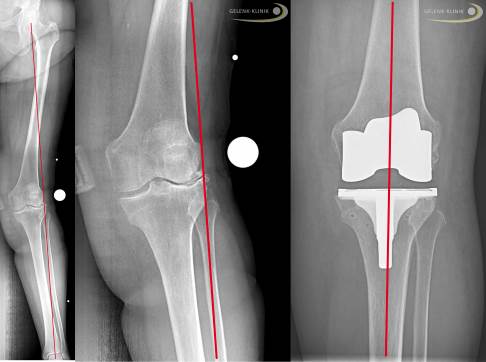

In ca. 90 % der Fälle, in denen eine Schlittenprothese eingesetzt wird, ist der innere Teil des Knies zwischen Oberschenkel und Schienbein betroffen. Oft ist eine Veränderung der Beinachse Ursache für diese Verschleißart des Kniegelenks. Die Beine sind zu einem O-Bein geformt, sodass der Hauptanteil des Körpergewichts auf der inneren Seite des Kniegelenks lastet. Man spricht von einer medialen Gonarthrose (Kniearthrose) bzw. im Falle einer schweren O-Bein-Stellung von einer Varusgonarthrose. In seltenen Fällen kann allerdings auch die äußere (laterale) Seite des Kniegelenks betroffen sein. Man spricht dann von einer lateralen Gonarthrose oder einer Valgusgonarthrose. Diese tritt oft im Zusammenhang mit bestehenden X-Beinen auf.